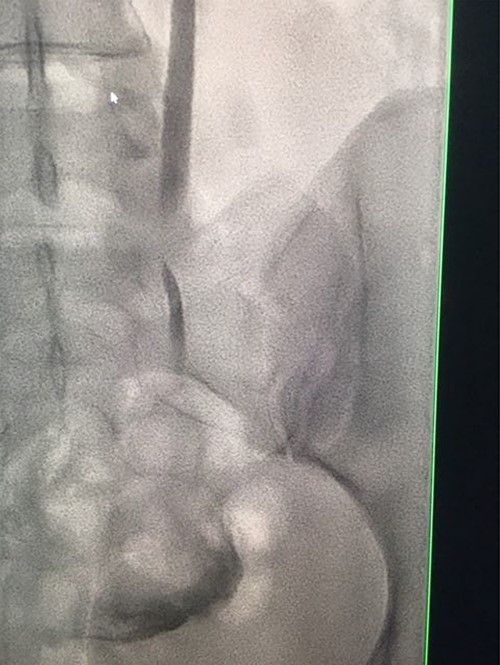

Under conscious sedation, using the previously inserted right percutaneous nephrostomy, antegrade access was achieved into the intrarenal collecting system and then into the proximal ureter. An 8 Fr × 11-cm access sheath was introduced. A guidewire was advanced antegradely through the site of ureteric transection and coiled in a position adjacent to the position of the guidewire that had been inserted retrogradely. A Gooseneck snare catheter was then passed over the guidewire and the snare was inserted (Figs 4 and 5). Under fluoroscopic guidance, the retrograde wire was retrieved and brought externally via the nephrostomy site, achieving through-and-through wire access (Figs 6 and 7).

Fluoroscopic images showing the antegrade Amplatz gooseneck snare catheter attempting to grasp the retrograde wire.